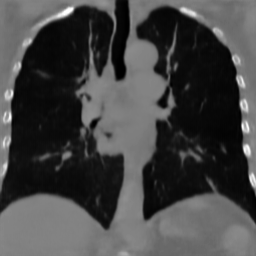

We demonstrate our model’s performance on two publicly available datasets: BraTS 2023 Adult Glioma [1, 2, 15, 20] and LIDC-IDRI [14]. For training on the BraTS dataset, we use the T1-weighted brain MR-images, clip the upper and lower 0.1 percentile intensity values, zero pad the volumes to a size of and normalize them to a range of . For training on the LIDC-IDRI lung CT dataset, we initially clip all values below and the upper 0.1 percentile intensity values. We then resample the images to an isotropic voxel size of 1 , center crop them to a size of , and normalize to a range of . When training on images with a resolution of , we perform downsampling by applying average pooling.

The results presented in Table 1 and 2 show our proposed method’s performance on unconditional 3D brain MR and chest CT image generation. Our proposed approach not only outperforms most comparing methods in FID and MS-SSIM metrics, it also has the lowest inference GPU memory footprint at a resolution of and was the only diffusion-based method that could be trained at a resolution of . Operating in the wavelet domain and profiting from the reduced spatial dimension also results in a relatively short inference time of / at the respective resolutions. Compared to the results presented in [23], we did not find that incorporating wavelet information into the network’s feature space (WavU-Net) increased the model’s performance. Qualitative results of our proposed method (WDM) are shown in Fig. 2 and 3. A qualitative comparison of samples produced by all evaluated methods can be found in the Supplementary Material.